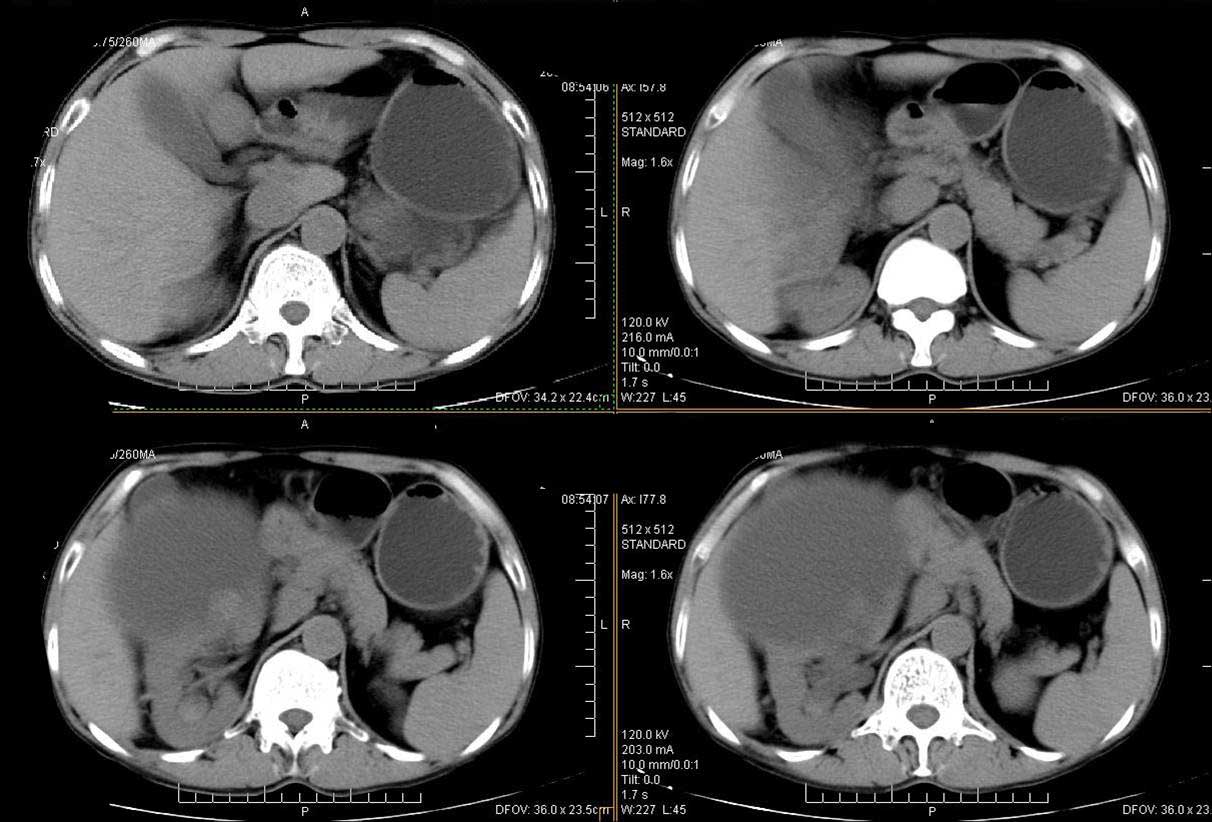

男性 60岁,腹部肿块4年余,肿块逐渐增大,活动性差,无血尿。

平扫

动脉期

门脉期